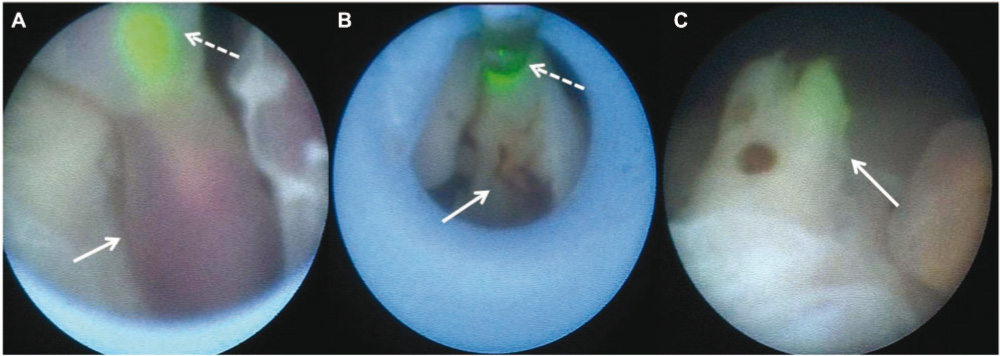

In view of the very unusual situation with a single pump twin, sustaining two growing masses, the parents chose early prenatal intervention. Laser coagulation with transection of the umbilical cords of both acardiaca was performed successfully at 15+6 weeks of gestation using a diode laser (D60 Multibeam Flexiplus, 20W; Dornier Medizintechnik, Wessling, Storz, Tuttlingen, Germany) in pulse and contact mode under direct fetoscopic view (7 French trocar and 1.3 mm fetoscope with 30.6 cm working length; Storz) (Figure 2). The procedure lasted for approximately 45 min and was performed under epidural anesthetics. Chromosomal studies performed on amniotic fluid revealed a normal female karyotype (46XX).

Fetoscopic view before, during, and after coagulation and transection of the umbilical cord using a diode laser.

White dashed arrows point to the green pilot light (A) and the laser fiber itself (B). White arrows show the umbilical cord of the acardiacus before (A), during (B), and after coagulation and transection (C).